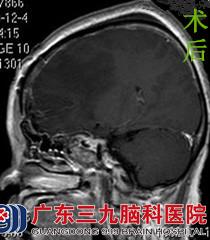

陈阿姨一家人来到广东三九脑科医院,行头颅MR检查提示右侧额部大脑镰旁示占位病变,大小约4.6cm×4.1cm×3.3cm,双侧脑室前角受压变窄,病变区域的中线结构明显向左侧偏移,鲁明主任考虑脑膜瘤可能性大。完善相关检查后,由鲁明主任主刀,在全麻下行右侧额部大脑镰旁脑膜瘤切除术,术中显微镜下见灰白色肿瘤,呈颗粒状,血供不丰富,质中,予肿瘤全切,手术顺利结束。术后经专科治疗护理,陈阿姨康复出院。术后病理结果:过渡型脑膜瘤。